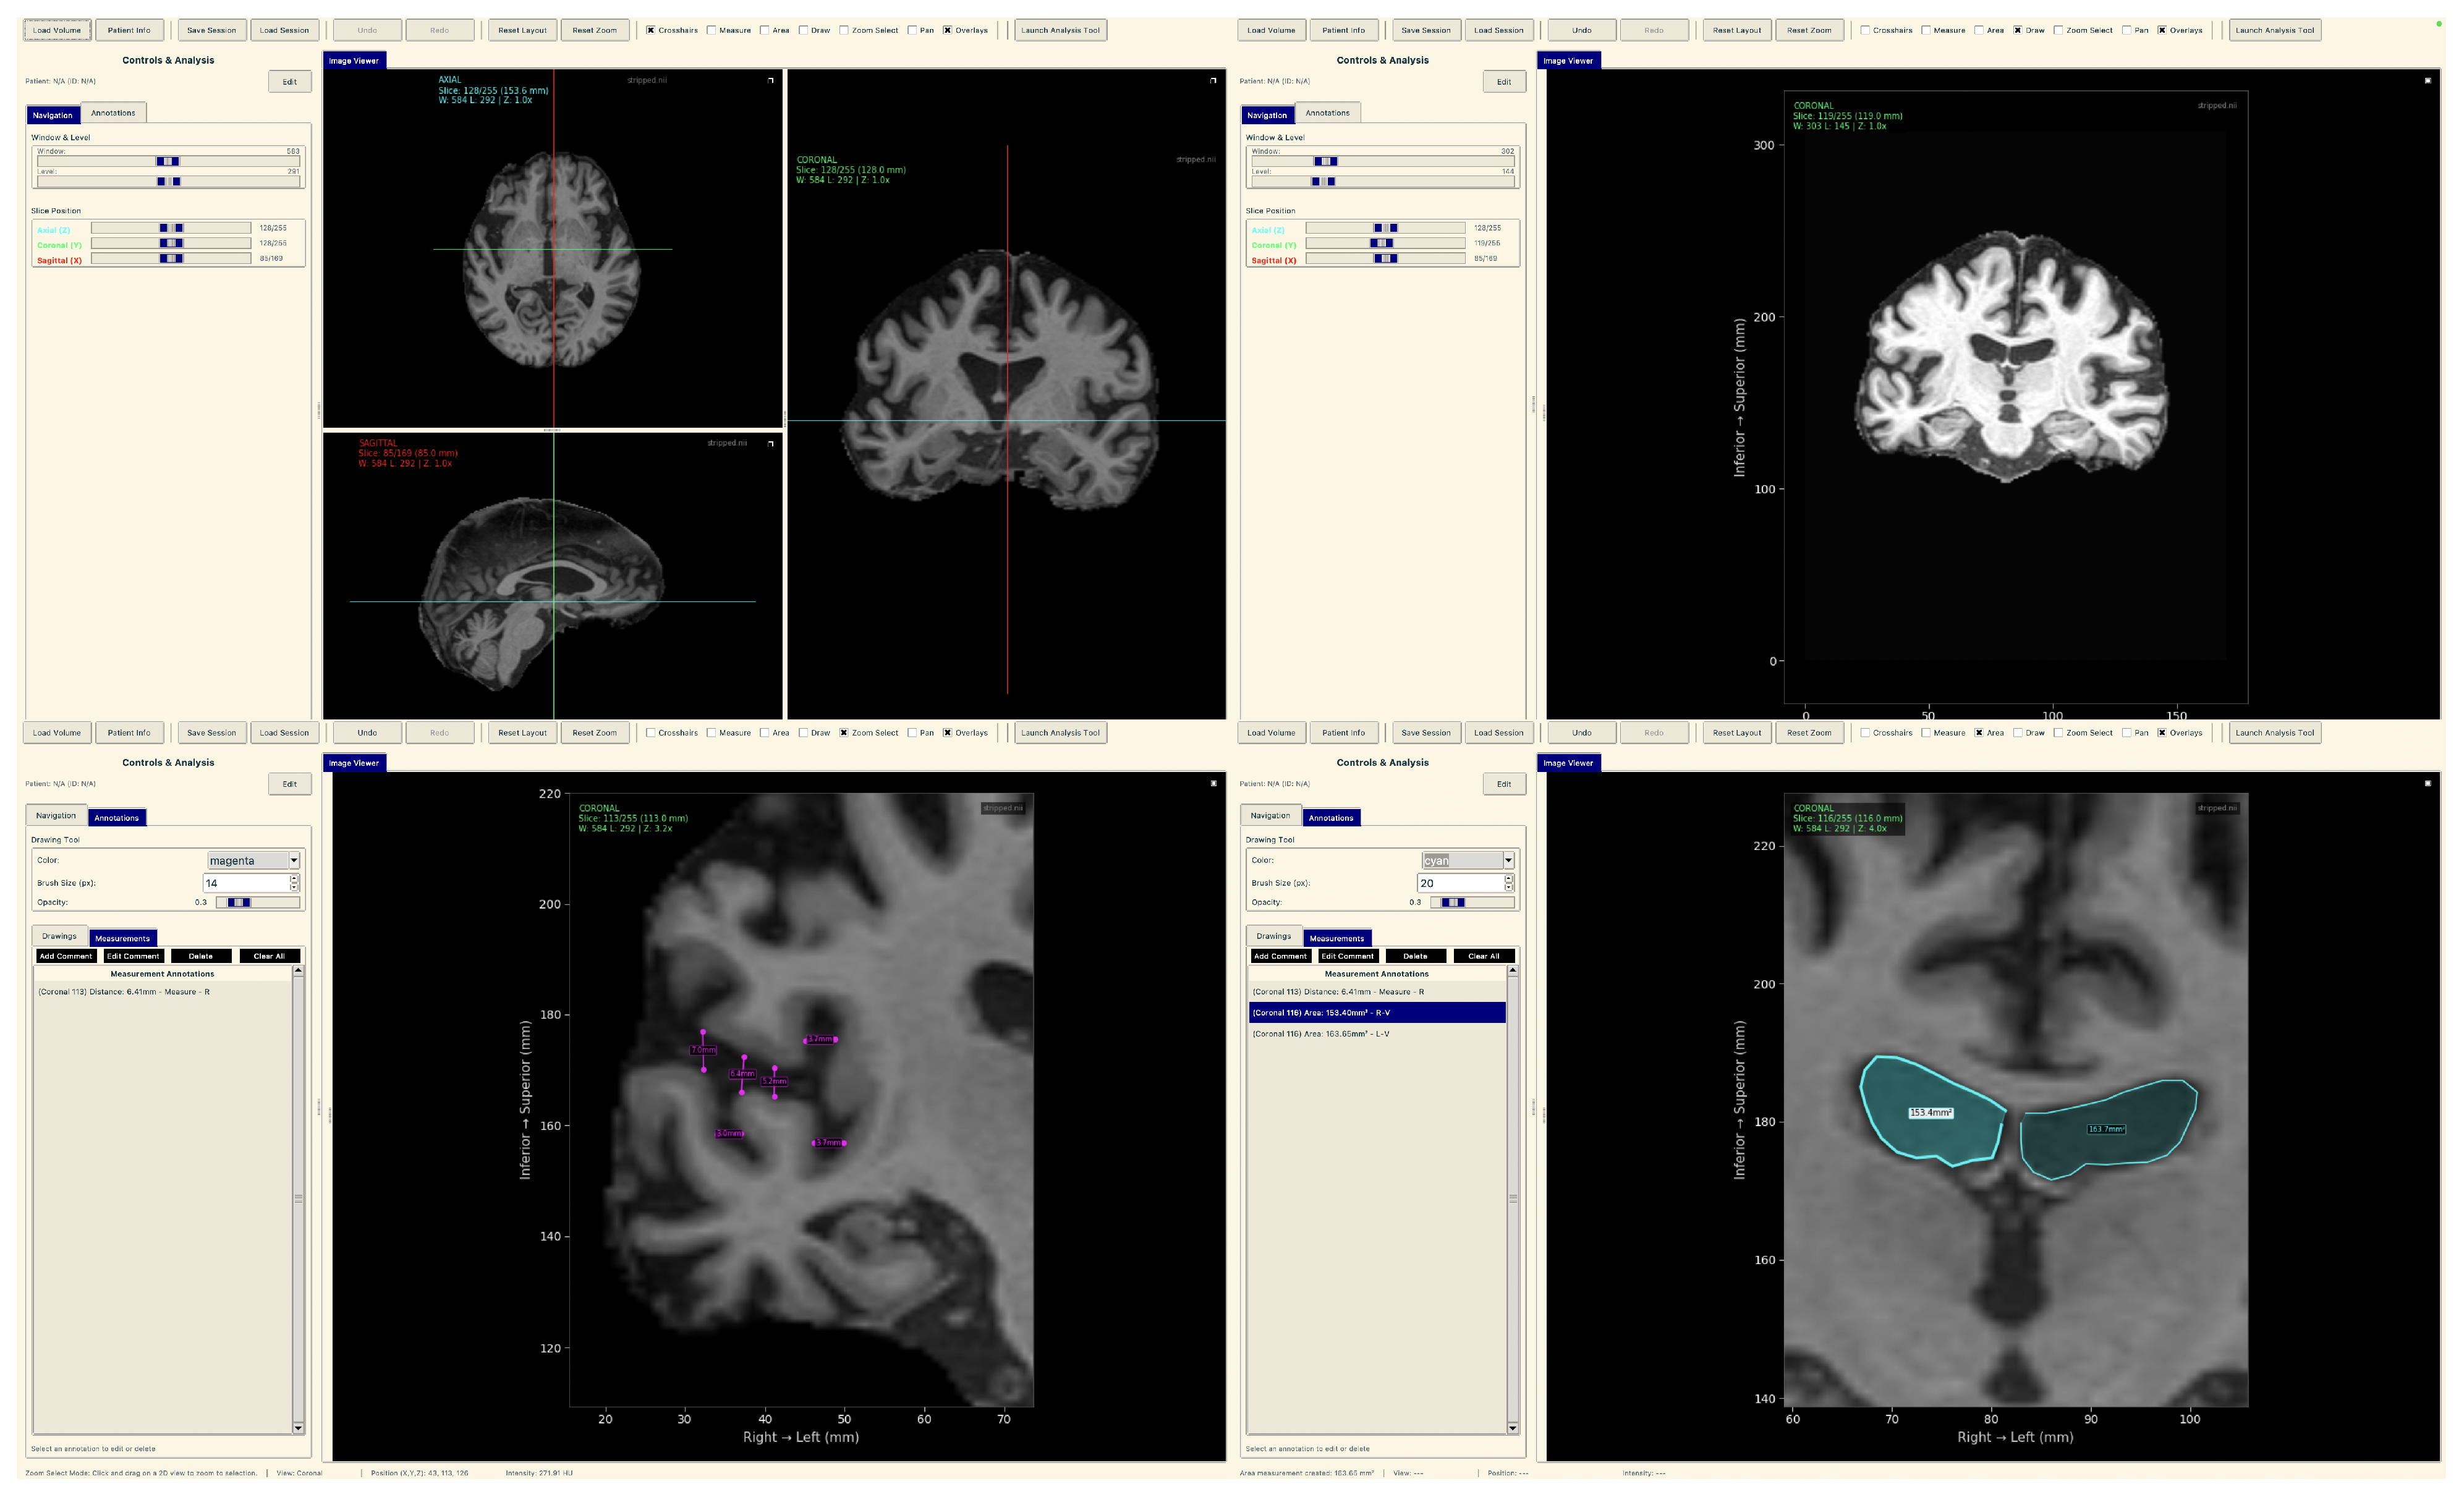

To demonstrate practical deployment of our lightweight explainable framework, we developed a neuroimaging analysis application that integrates our trained models with real-time explainability visualization for clinical evaluation workflows.

The tool consists of two main components: a comprehensive slice viewer for medical image navigation and annotation, and a specialized XAI analysis module for model inference and explainability visualization. The slice viewer implements medical imaging functionality including multi-planar viewing, window/level adjustment, measurement capabilities, and annotation tools using Python 3.11.3 with SimpleITK 2.5.2 for medical image handling and TensorFlow for neural network execution. The analysis module integrates our best model, the EfficientNetV2B0 model trained on augmented data with configurable layer selection for different explainability methods. The system includes dynamic layer configuration interfaces that automatically detect convolutional layers in loaded models and enable users to specify attribution layers for Grad-CAM++, Guided Grad-CAM++, and consensus attribution maps across different architectures.

The tool consists of two main components: a comprehensive slice viewer for medical image navigation and annotation (Figure 30), and a specialized XAI analysis module for model inference and explainability visualization (Figure 31). The slice viewer implements medical imaging functionality including multi-planar viewing, window/level adjustment, measurement capabilities, and annotation tools using Python with SimpleITK for medical image handling and TensorFlow for neural network execution.

Figure 30.

Neuroimaging slice viewer interface demonstrating MRI visualization capabilities.

Figure 31.

Analysis tool interface demonstrating AI explainability features.

The analysis tool implements a simplified preprocessing pipeline suitable for demonstration purposes, including basic cropping and resizing to the required input dimensions . The complete preprocessing pipeline described in the data set and preprocessing (Section 3.1) should be applied before using this tool.

The application maintains computational efficiency suitable for standard clinical hardware while providing session management, annotation capabilities, and structured reporting. The modular architecture supports both clinical demonstration and research validation, enabling comparative studies of lightweight architectures within a consistent framework. The complete implementation serves as a proof-of-concept for the deployment of accessible AI tools in routine clinical settings.